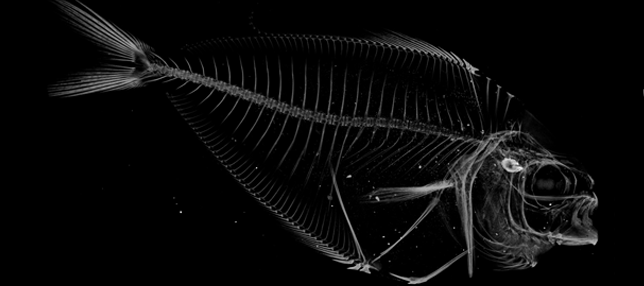

Micro-computed tomography (μCT) is a three-dimensional, X-ray-based imaging modality that can image tissues, organs and whole organisms as well as nonorganic structures with a spatial resolution as high as 6-10 μm. μCT systems provide rapid, quantitative, high-resolution and three-dimensional assessment of both microstructure and density. μCT is nondestructive and can scan ex-vivo samples as large as 75 cubic centimeters in several hours.

The Micro-Computed Tomography Imaging Core Facility at BU has one μCT scanner and one X-ray microscope. The μCT scanner is a Scanco μCT40 system which is density calibrated on a weekly basis to keep our scans accurate. The XRM is the Zeiss Xradia Versa 520. We have multiple software options that allow for the identification of sub-regions for image segmentation, registration, and quantitative analysis. Analyses can be performed on three-dimensional regions of interest to quantify porosity, thickness, and other features of the microstructure. Additionally, two-dimensional regions of interest can be analyzed to quantify bone area, bone area fraction, cross-section area, and moment of inertia. We have the ability to render and export images in a variety of file formats.